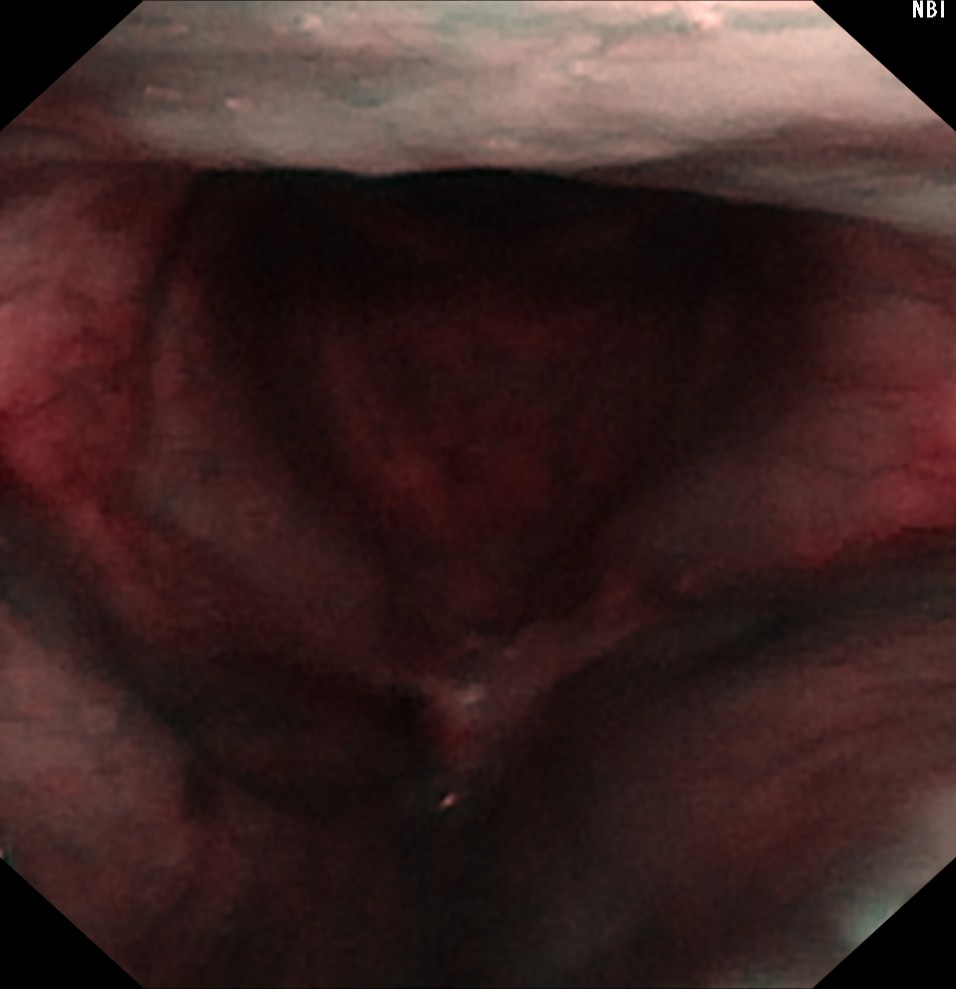

术后2个月后,张大叔返院复查,声嘶较前明显好转!复查电子喉镜如下图,左图为普通喉镜示:双侧声带区光滑,未见明显肿物复发!右图为NBI喉镜提示:未见有恶性肿瘤复发血管紊乱表现。